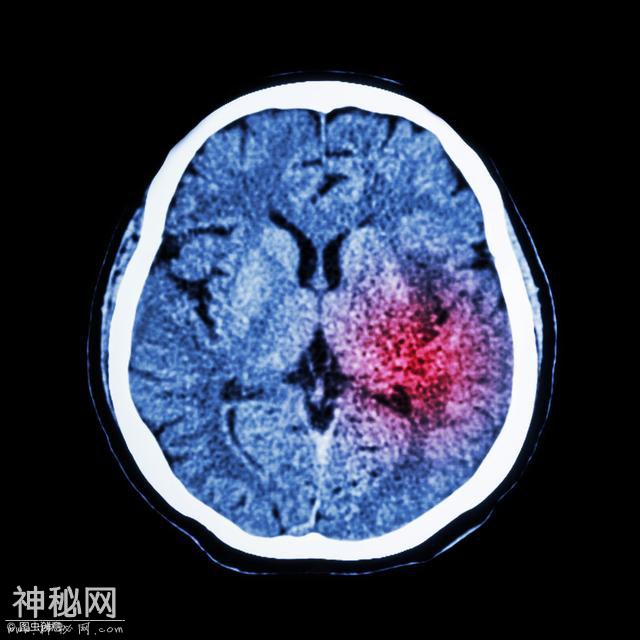

脑梗塞患者怎么饮食保健?脑梗塞出现之后,我们的身体会受到比较大的影响,所以我们应该注意积极的进行治疗,这样才可以保证我们的身体健康,并且在治疗的同时我们还需要注意做好日常的饮食保健,那么脑梗塞患者怎么进行饮食保健呢?下面我们就一起了解一下吧!